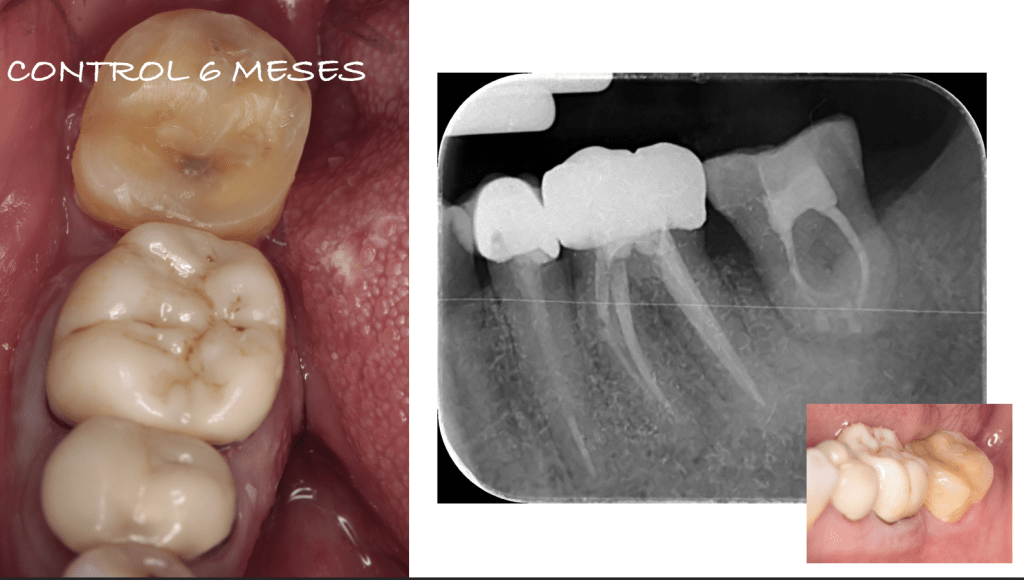

REIMPLANTES

Reimplante, istmo apical, curación cortical palatina 1 año